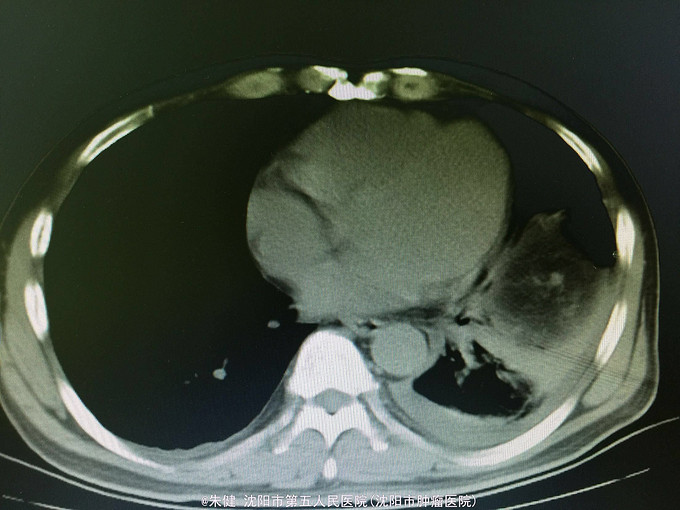

一般状态可,腹部平坦,未见肠形及蠕动波,剑突下及左侧上腹部压痛,轻度肌紧张,未及包块,无移动性浊音,肠音正常,肾区无扣痛。 辅助检查:血常规:白细胞13.6*10^9/L,中性83.3/L;尿淀粉酶:214U/L,上腹部CT:左侧胸腔积液,左肺下叶可见斑片及索条状影;胆囊增大,胆道内未及结石影;胰腺形态及密度正常,胰腺尾部周围可见索条状影及积液影。

诊断:急性胰腺炎 处理:给予禁食、补液、抗炎及抑肽酶治疗,病情逐渐好转,一周后出院。